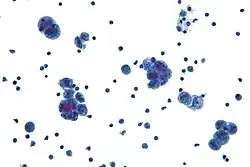

| Micrograph of serous carcinoma, a type of serous tumour. |

A serous tumour is a neoplasm that typically has papillary to solid formations of tumor cells with crowded nuclei, and which typically arises on the modified Müllerian-derived serous membranes that surround the ovaries in females. Such ovarian tumors are part of the surface epithelial-stromal tumour group of ovarian tumors. They are common neoplasms with a strong tendency to occur bilaterally, and they account for approximately a quarter of all ovarian tumors.